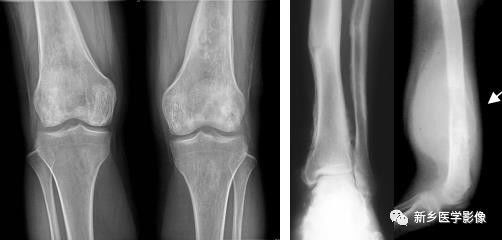

骨质破坏X线图像

a. 膝部X线侧位片示胫骨上段不规则溶骨性破坏,局部见软组织肿块。b.肘关节正位片示尺骨上段膨胀性骨质破坏,边缘骨质硬化,无软组织肿。

骨质破坏见于炎症、肉芽肿、肿瘤或肿瘤样病变。由于病变的性质、发展的快慢和邻近骨质的反应性改变不同,不同病因造成的骨质破坏在X线表现上具有一定的特点。如在炎症的急性期或恶性肿瘤,骨质破坏常较迅速,轮廓多不规则,边界模糊,可称为溶骨性破坏。而炎症的慢性期或良性骨肿瘤,则骨质破坏进展较缓慢,边界清楚,在骨破坏区边缘往往可见一致密的骨质增生硬化带围绕;如造成骨轮廓的膨胀,可称为膨胀性骨破坏。

骨质破坏CT图像

a. 髋股部CT冠状面重组图像示右股骨上段骨髓腔内骨质破坏,呈膨胀性改变,周围骨质硬化;b. 小腿上段CT横断面图像示右侧胫骨大片骨质破坏、缺损,局部软组织肿块。